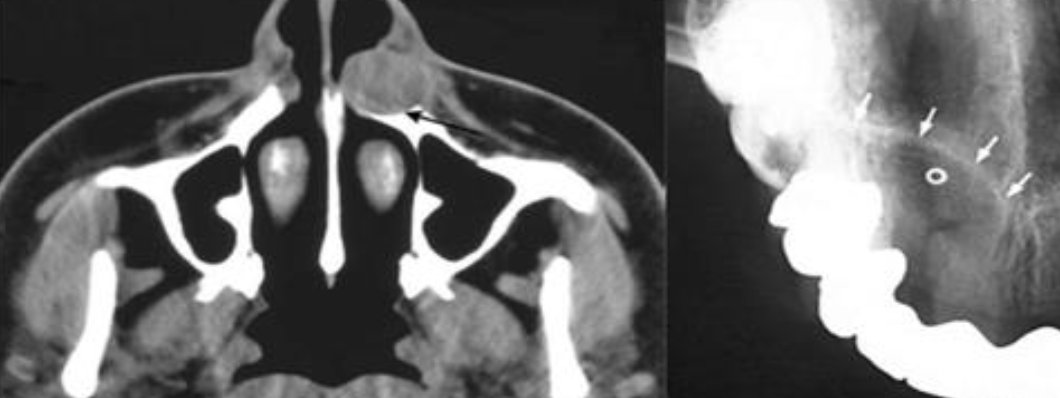

| Periapical(radicular) cysts | Rest of Malassez 被刺激 | - | - | true/ periapical cyst 圓形的光通性包圍根尖 |

牙根吸收, 2cm ↑ 根管治療無效  |

Nasopalatine duct cyst |

Nasopalatine duct 上皮的殘留 | 顎部前 | 40-60y | 藍 |

牙根吸收 |

| 多種上皮, cilia, goblet cell, 神經和血管可見 | ||||

Incisive canal cyst |

NDC 特例 | Incisive papilla 內 |

φ < 6mm | |